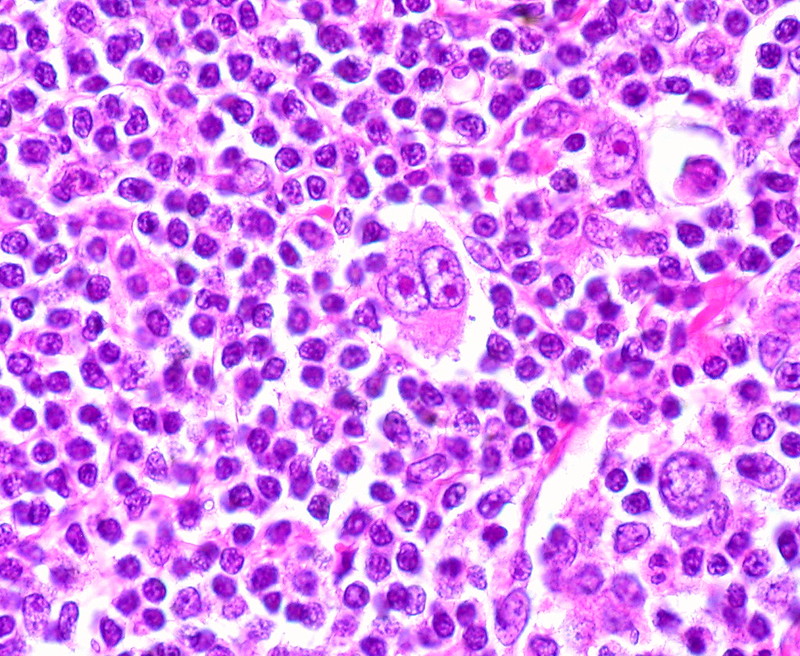

El linfoma de Hodgkin es un tipo de cáncer que afecta al sistema linfático, un sistema de transporte similar al aparato circulatorio que forma parte del sistema inmunitario. Este tipo de linfoma se origina en los linfocitos B, un tipo de célula inmunitaria, y se caracteriza por la presencia de unas células anormales llamadas células de Reed-Sternberg, visibles al microscopio. Supone cerca del 10% de todos los linfomas y es más frecuente en personas jóvenes entre 15 y 35 años, y en mayores de 55, aunque puede aparecer a cualquier edad.

Representa aproximadamente el 95% de los casos. Se caracteriza por la presencia de células de Reed-Sternberg con un fenotipo alterado y un entorno tumoral inflamatorio. Se divide en cuatro subtipos según el patrón histológico:

La prueba principal inicial es la biopsia de un ganglio linfático afectado. Este procedimiento consiste en extraer una muestra del ganglio para analizarla al microscopio. Si se identifican las células características del linfoma de Hodgkin —las células de Reed-Sternberg— se confirma el diagnóstico. La biopsia debe ser completa y no por aspiración con aguja fina, ya que es necesario estudiar la arquitectura del tejido.